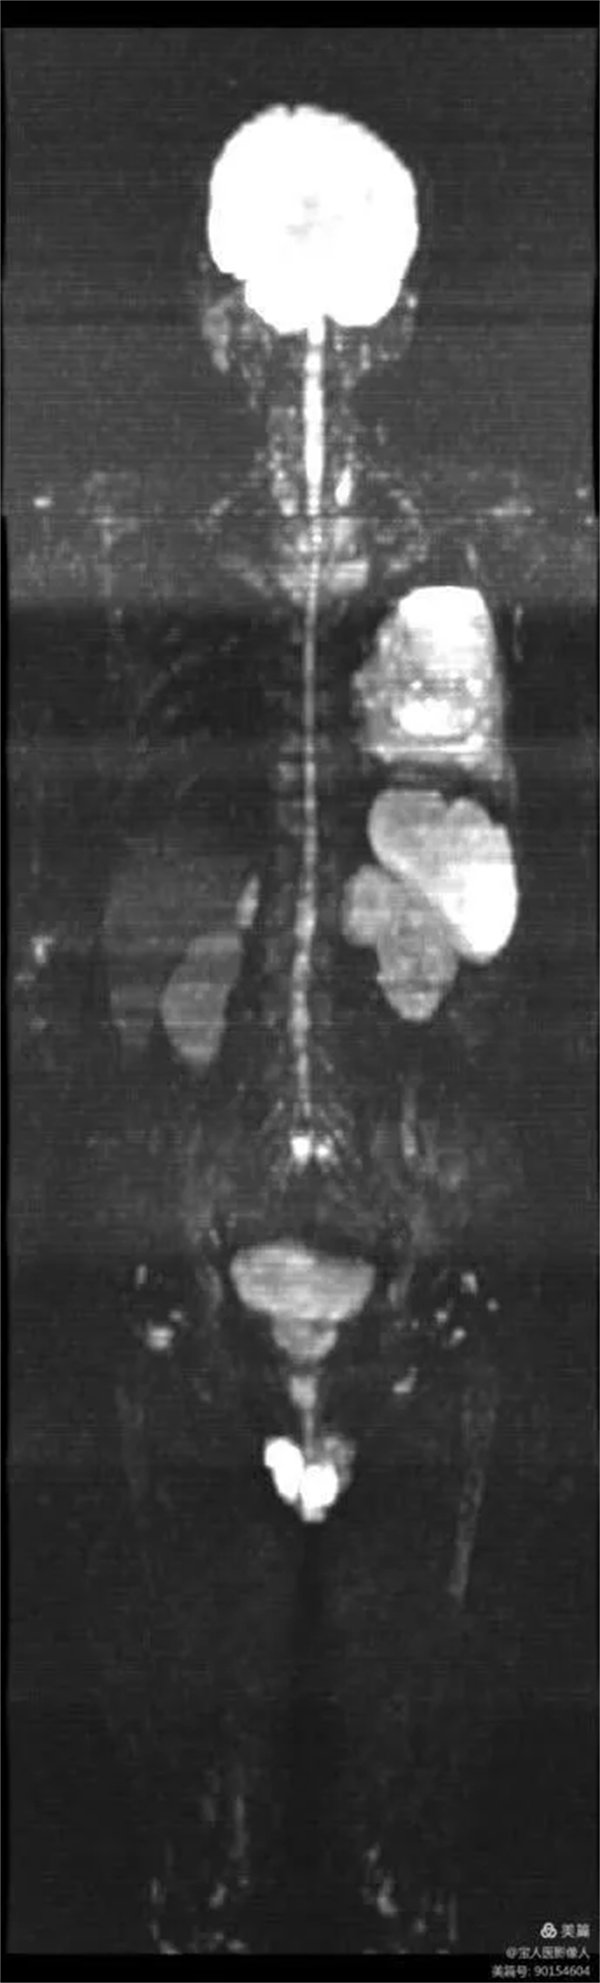

圖1:全身彌散成像圖像

磁共振全身彌散加權(quán)成像(WB-DWI),是將彌散加權(quán)成像技術(shù)與自動拼接技術(shù)和全景成像矩陣相結(jié)合而獲得全身的彌散加權(quán)成像影像。所得影像經(jīng)黑白翻轉(zhuǎn)后可達(dá)到與正電子發(fā)射計(jì)算機(jī)體層顯像(PET)影像類似的效果,故被稱為“類PET”,是近年來發(fā)展起來的全新影像檢查新技術(shù)。

該技術(shù)能夠進(jìn)行全身大范圍掃描,并加以3D后處理重建,可獲得全身腫瘤篩查、良惡性腫瘤的鑒別、腫瘤TNM分期及療效隨診等診斷信息,全身彌散技術(shù)把肌肉、脂肪、肝臟等組織背景信號抑制掉,突出了病變的顯示,大大提高了病變組織尤其是惡性腫瘤及其轉(zhuǎn)移灶的檢出率。